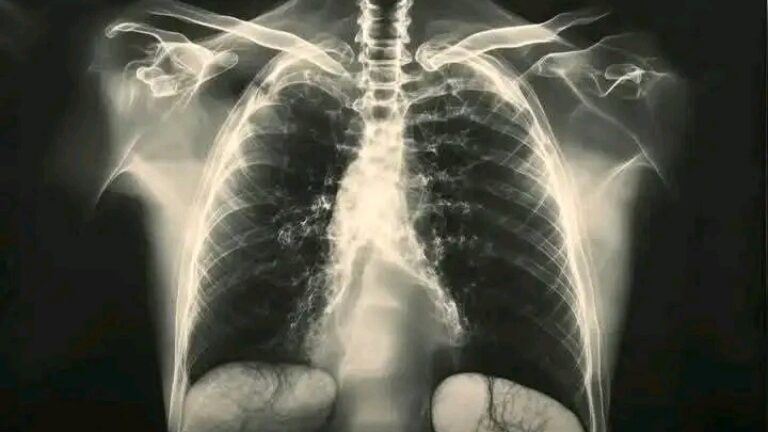

COVID 19. Alerta mundial

COVID 19. Alerta mundial vacunados

UltimaHora_COVID_19 Alerta Mundial para